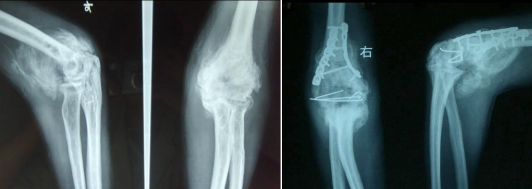

1. 早期(伤后几周):关节红、肿、热、痛加剧,活动度下降,X光常无异常。

2. 成熟期(数月到一年):疼痛减轻,僵硬突出,X光可见钙化影逐渐形成清晰骨块。

3. 稳定期(一年后):骨块成熟定型,关节活动度永久性部分丧失。